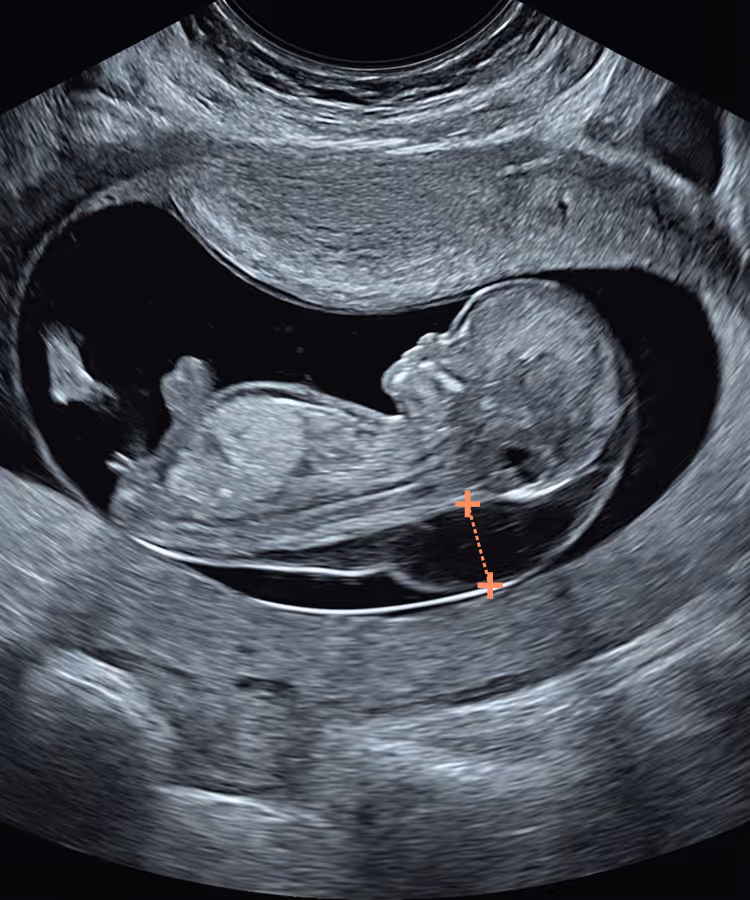

At 10 weeks the fetus is roughly half the size of a 12-week fetus and anatomically immature. Standard Fetal Medicine Foundation (FMF) and NHS criteria are therefore not applicable at 10 weeks, as key landmarks are absent and fetal proportions differ. We have introduced dedicated 10-week criteria based on a full-body crown–rump length (CRL) image in a true mid-sagittal view. This differs from the FMF “head-and-thorax fill-the-screen” magnification; otherwise, the NT measurement technique is similar to FMF. These early NT criteria apply when CRL <45 mm; for CRL ≥45 mm, use the standard FMF criteria.

You simply cannot apply the classic 11–14-week NT rules to a 10-week fetus, which is why we developed specific 10-week NT criteria. At 10 weeks the fetus is smaller, has different proportions and is structurally less mature than at the standard 12-week scan.

This becomes especially important when you are trying to measure a significantly increased NT. You cannot zoom in to a strict “head–chest” view as recommended later in the first trimester, because the whole fetus will not fit the screen and excessive magnification makes the NT borders blurred and difficult to measure accurately. At 10 weeks the fetus is also missing some key landmarks used later, such as the nasal bone.

Using a CRL-type sagittal image rather than a classic NT-type view optimises workflow, reduces scanning time and fetal exposure, and frees more time to assess vital structures such as the brain and spine.